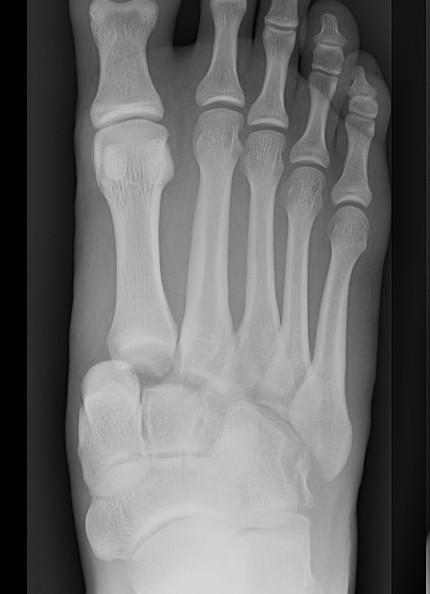

Classification

| Isolated | Homolateral | Divergent |

|---|---|---|

| Only 1st MT injured / displaced | All 5 metatarsals displaced in same direction |

1st metatarsal displaces medially Other 4 metatarsals displace laterally |

| Most common | Least common | |